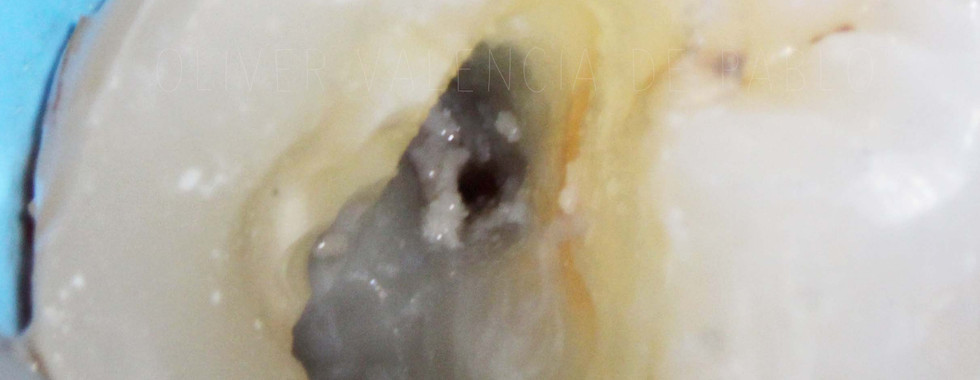

En esta ocasión el paciente presentaba molestias intensas con el frío, y también percusión positiva. El diagnóstico fue de pulpitis irreversible pero, como se puede apreciar claramente en la imagen, había diferente estado pulpar en las distintas raíces. Mientras que la raíz distovestibular presentaba necrosis pulpar, las mesiovestibular y palatina mostraban un sangrado profuso, característico de una inflamación inrreversible.

Búsqueda del cuarto conducto

Siempre que iniciamos el tratamiento de endodoncia en un primer molar superior, debemos tener presente que es muy probable que exista un cuarto conducto. En esta ocasión, tras explorar cuidadosamente la cámara pulpar no se veían rastros de su existencia pero al emplear la magnificación del microscopio dental, observamos un pequeño surco que nacía del conducto MV. Tras explorarlo con puntas ultrsónicas finas, localizamos allí la entrada del conducto mesiopalatino. A pesar de su cercanía con el mesiovestibular, como podemos observar en las radiografías finales, tiene un recorrido totalmente independiente.